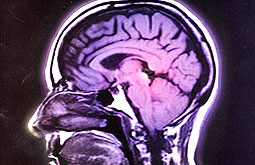

Accidentes cerebrales asintomáticos son habituales en la población sana

Para los autores de la investigación, los incidentes cerebrales detectados por resonancia magnética en la población general suelen ser muy comunes. Los hallazgos más frecuentes son infartos cerebrales, seguido de aneurismas y tumores benignos. Es...